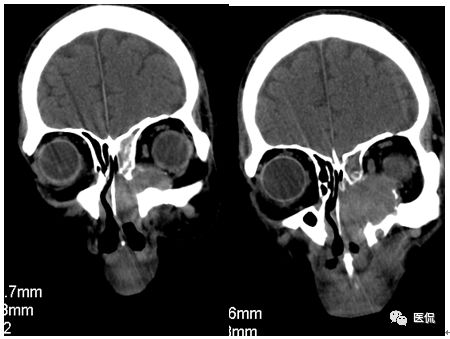

CT平扫及增强示:左侧上颌窦及鼻腔可见软组织密度影,呈膨胀性生长,周围骨质压迫性吸收破坏,累及左眶,病灶密度不均匀,周边区可见点状钙化,增动脉期轻度强化,局部见小灶性稍高密度区,静脉期病灶内见不均匀明显强化,CT值最高达117HU,延迟期强化范围有所增大。

本例病灶较大,周围骨质可见吸收破坏,并累及眼眶,病灶内少量钙化,增强扫描具有一定特征性,表现为动脉期轻度强化,局部见小灶性稍高密度区,静脉期病灶局部呈明显强化,CT值最高达117HU,延迟期强化范围有所增大,呈延迟渐进性强化的特点,推测为病灶内出血所致。